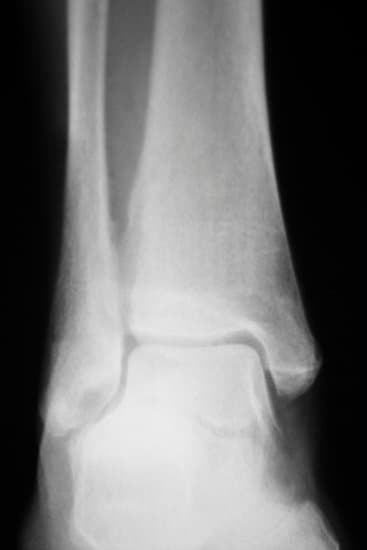

외상 후 관절염: 골절과 같은 심각한 발목 부상 후 발생한 경우.

유합: 발목을 구성하는 뼈들을 정렬하고 금속 판, 나사, 또는 막대를 사용하여 고정합니다. 이는 뼈가 자연스럽게 융합될 수 있도록 안정성을 제공합니다.